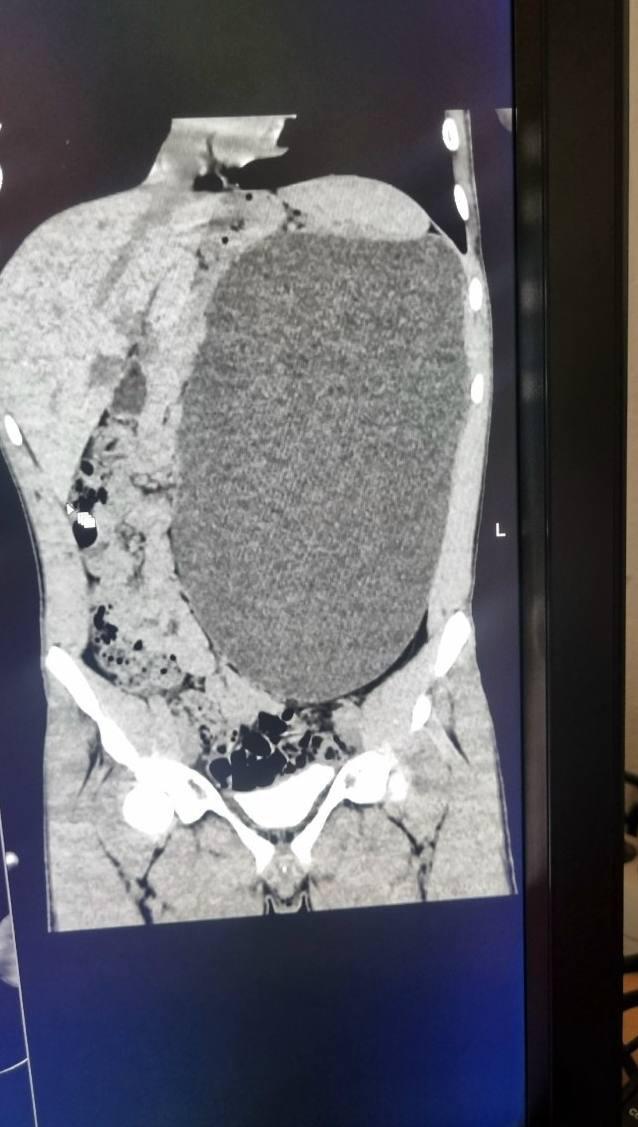

В Новосибирске у подростка удалили почку размером с пятилитровую бутылку Как отметили в больнице это была настоящая бомба замедленного действия случайный удар в живот и мешок мог разорваться До обследования подросток не испытывал никаких симптомов и считал себя полностью здоровым Фото Telegram канал Министерства здравоохранения Новосибирской области

Почка размером с пятилитровую бутылку выросла у подростка Образование заняло почти весь живот и сдавливало внутренние органы При этом 17 летний парень из Новосибирска не чувствовал никаких симптомов и считал себя абсолютно здоровым Любой сильный удар в живот мог закончиться очень плохо Четыре дня врачи откачивали жидкость а затем удалили поражённую почку сейчас подросток идёт на поправку НМШ

У подростка обнаружили почку размером с пятилитровую бутылку Она занимала почти весь живот и сдавливала остальные органы 17 летний новосибирец не испытывал никаких симптомов и считал себя полностью здоровым Врачи нашли патологию случайно и назвали её бомбой замедленного действия случайный удар по животу мог привести к разрыву этого образования В течение четырёх дней хирурги откачивали скопившуюся жидкость а затем удалили поражённую почку Сейчас пациент идёт на поправку хорошо что всё закончилось благополучно Подпишись на Ленту дня в MAX Участвуй в розыгрыше